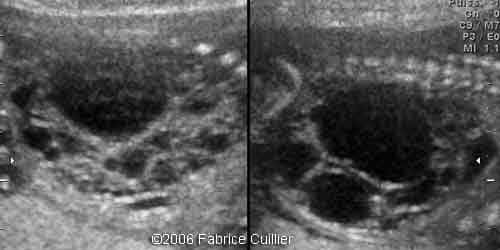

2D transverse view at 17 weeks showing bilateral hyperechoic kidney with no corticomedullary differentiation

1A.

1B.